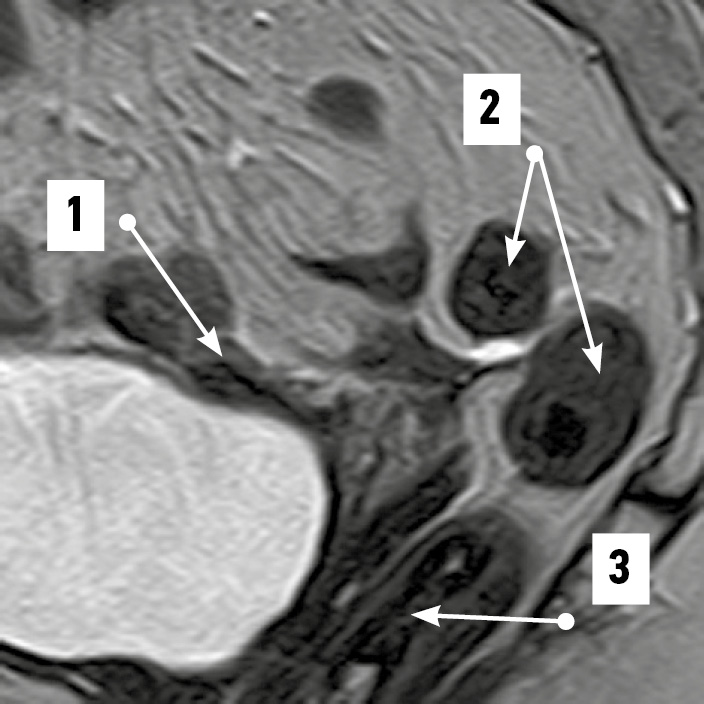

По результатам МРТ-анализа при положениях матки anteversio-anteflexio надвлагалищный участок прямой кишки в половине случаев (52,4%) был извит во фронтальной плоскости (рис. 1). В 38,1% случаев кишка имела ход, соответствующий вогнутости крестца (рис. 2), ещё в 9,5% сагиттальный изгиб кишки был значительно выражен. Расстояние между маткой и прямой кишкой в надвлагалищном участке в среднем составило 5,93±0,97 мм. Здесь прослеживался значительный разброс минимальных и максимальных величин, свидетельствовавший о разнообразии положения органов: от их крайней степени близости — 0,00 мм (рис. 3) до удалённого положения — 17,00 мм (рис. 4). Последнее может служить анатомической предпосылкой для положения петель тонкой кишки в относительно широком прямокишечно-маточном углублении.

Рис. 2. Изгиб надвлагалищного участка прямой кишки, соответствующий тазовой поверхности крестца. Магнитно-резонансная томограмма органов таза в режиме SG T2: 1 — матка; 2 — прямокишечно-маточное пространство; 3 — надвлагалищный участок прямой кишки, соответствующий вогнутости крестца; 4 — влагалищный участок прямой кишки. / Fig. 2. Convolution of the supravaginal segment of the rectum, corresponding to the pelvic surface of the sacrum. SG T2-magnetic resonance imaging of pelvic organs: 1 — uterus; 2 — rectal–uterine space; 3 — supravaginal segment of the rectum corresponding to the sacrum concavity; 4 — vaginal segment of the rectum.